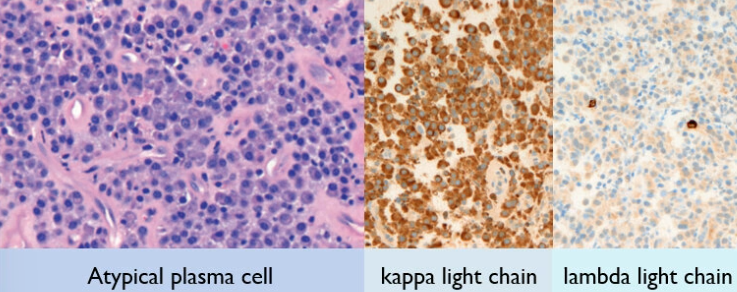

Solitary Plasmacytoma 單一漿細胞瘤

過多免疫球蛋白堆積在細胞質

- 非典型漿細胞(atypical plasma cells)

- 細胞質較多且偏藍紫色

multiple myeloma

Plasma cell 大小不一

κ chain 超多 (10:1) → 來自單株